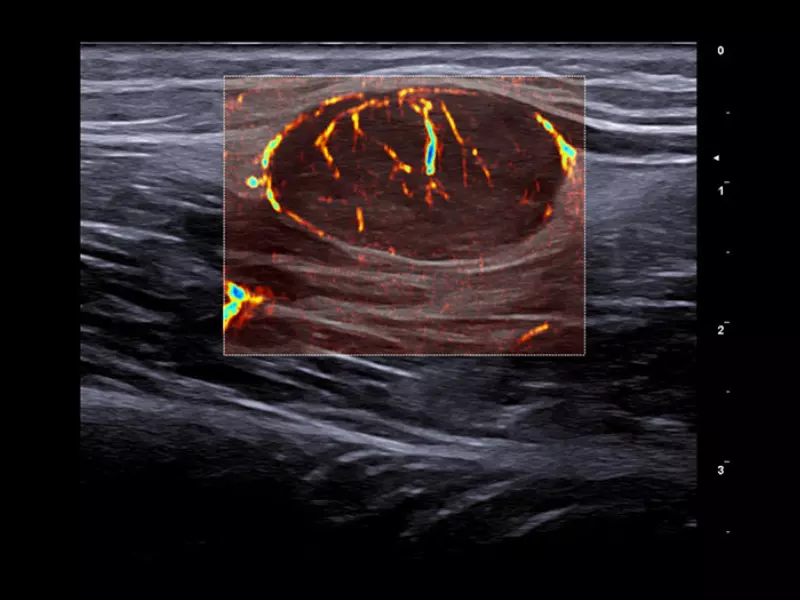

MyLab™9 Platform - XFlow in testis vascularization

MyLab™9 Platform - XFlow in testis vascularization